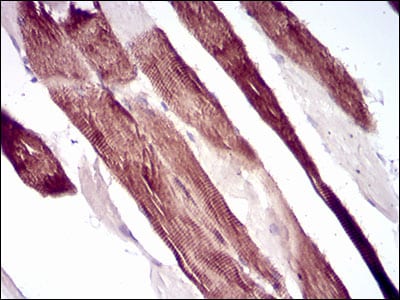

分类: 科研抗体货号: 30706别名: TRIM63; IRF; SMRZ; MURF2; RNF28应用: IHC反应种属: Human